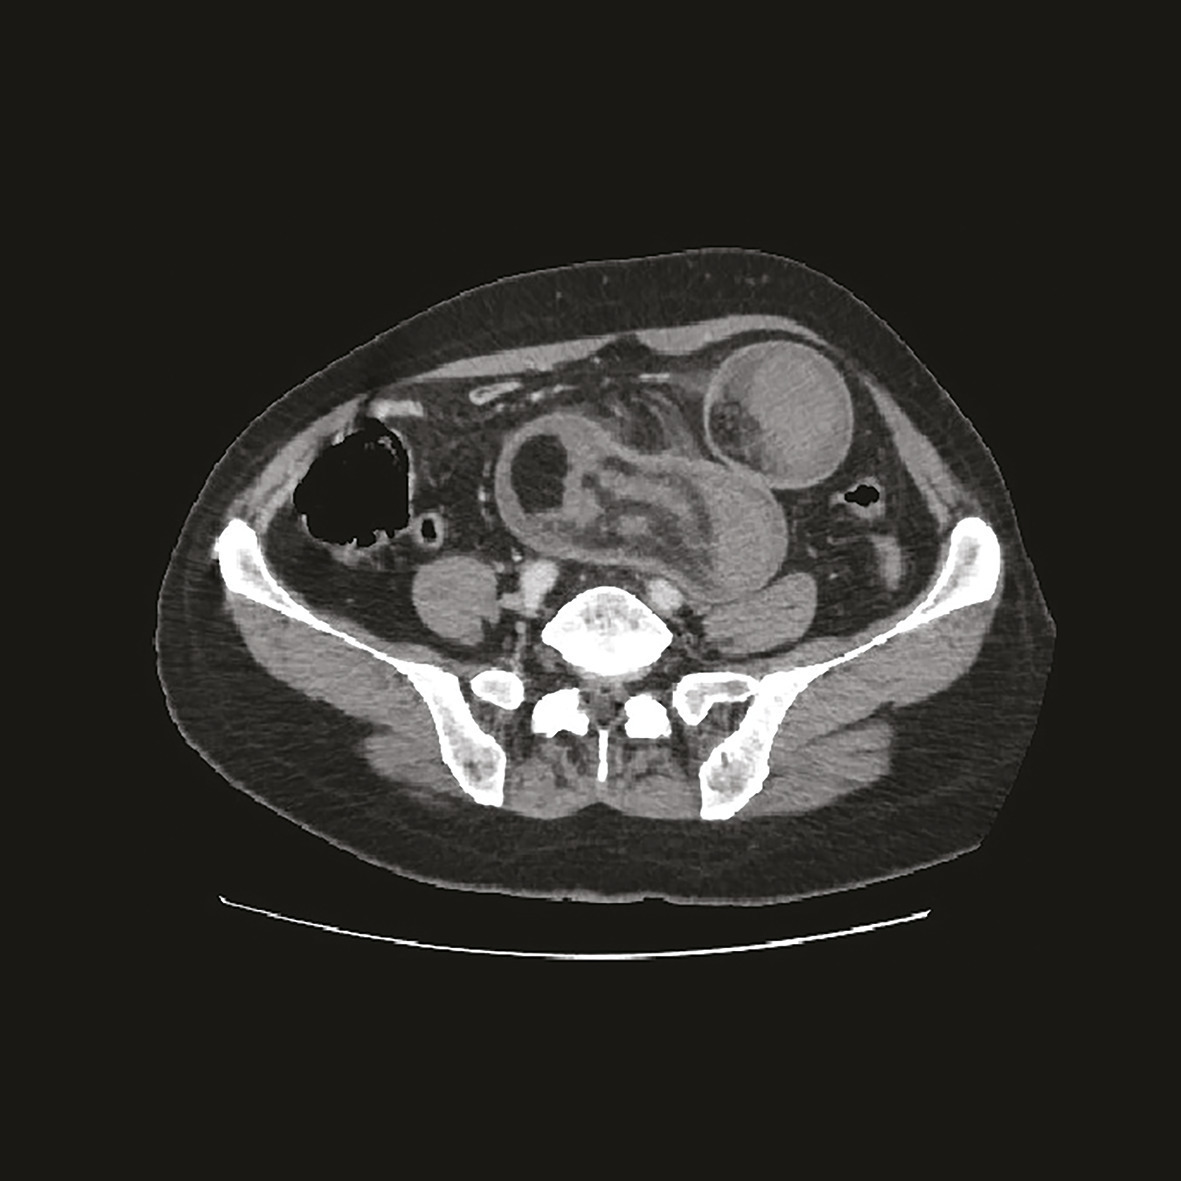

Cette femme de 62 ans était admise aux urgences pour des douleurs abdominales, des vomissements alimentaires et un arrêt des gaz, depuis 2 jours, sans fièvre. Elle avait pour antécédents une gastrite chronique, des douleurs abdominales intermittentes chroniques. L’examen notait une distension abdominale, une sensibilité abdominale diffuse ; les orifices herniaires étaient libres et l’ampoule rectale vide, sans melaena ni rectorragies. La pression artérielle était à 130/70 mmHg. L’échographie abdominale montrait une masse de la fosse iliaque gauche. La tomodensitométrie (TDM) abdominale révélait une masse ovalaire, hypodense, multistratifiée, avec un aspect en cocarde, ayant en son sein une incarcération mésentérique et en périphérie une lésion graisseuse en rapport avec un lipome (fig. 1 ). Le diagnostic d’invagination iléo-iléal secondaire à un lipome était évoqué. Une résection chirurgicale de 100 cm de grêle était réalisée (fig. 2 ).

L’invagination intestinale est définie par le télescopage et la pénétration d’un segment intestinal dans le segment d’aval. Elle survient essentiellement chez le nourrisson (80 % entre 6 mois et 2 ans).1 L’atteinte de l’adulte est rare. Selon les études précédentes, 1 et 5 % des invaginations intestinales aiguës s’observent chez l’adulte contre plus de 95 % chez l’enfant. Un lipome en est exceptionnellement la cause.2 Le diagnostic se fait par l’imagerie, plus rarement par la chirurgie. La TDM montre une masse tissulaire avec une alternance de zones concentriques en cocarde surmontée d’une image en croissant excentrée de densité graisseuse correspondant au boudin.1 Le traitement est chirurgical chez l’adulte, les causes organiques sous-jacentes étant les plus fréquentes.